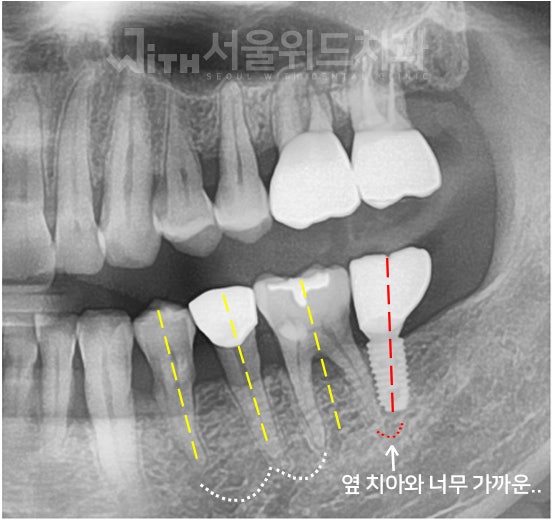

많은 분들이 치아가 상실되는 문제를 겪고 있다 하더라도 원인, 상실된 기간, 구강 환경 등에 따라 다양한 방법의 임플란트가 적용될 수밖에 없다는 사실을 알아야 했습니다. 경험이 부족한 전문의와 함께하면 이러한 니즈를 고려할 수 없게 되고 결국 만족도가 낮아질 수 있기 때문에 고난도 임플란트 시술도 잘하는 전문의와 함께하여 건강한 구강 환경을 오래 유지할 수 있도록 해야 했습니다.게다가 잇몸뼈 상태를 확인하는 것도 중요하다고 생각해야 하는데 총 2회에 걸쳐 잇몸뼈 상태를 확인해야 보다 안정적인 수술을 할 수 있기 때문입니다. 따라서 이러한 과정을 거쳐 길고 안정적으로 사용할 수 있는 임플란트를 완성해야 했습니다.치아가 탈락하지 않고 단순히 손상된 경우에는 전악보철 풀마우스를 고려하는 것이 좋으나 이는 치아를 발치하여 식립하는 것이 아니라 신경치료와 지르코니아 크라운을 통해 전악을 재건하는 것이므로 자연치아 상실을 막으면서 잃어버린 심미성과 기능성을 되찾을 수 있다는 장점이 있었습니다.공석을 대체하는 것은 환자에게 단 한 번의 기회였을지도 모릅니다. 따라서 치과 선택이나 치료 방향을 설정하는 과정에 매우 신중해야 하지만 분당 임플란트를 해야 하는 상황임에도 불구하고 통증과 이차적인 문제에 대한 두려움으로 조치를 미루고 있다면 내비게이션 임플란트를 고려해 보면 좋은 시도가 되었습니다.내비게이션 임플란트는 기존 아날로그 인상 획득과 같은 불편한 과정 없이 임플란트를 완성할 수 있다는 장점을 가지고 있으므로 특히 신체적 기능이 약한 분들은 이러한 방법을 적극 이용해야 함을 알려드립니다.앞서 말했듯이 무절개로 적은 통증만으로 빠르게 시술할 수 있는 것은 사실이지만 무분별한 무절개는 오히려 임플란트를 오래 사용하지 못하게 할 수 있기 때문에 절개 여부는 의료진과 충분히 상의한 후 결정하도록 해야 했습니다.그리고 식립 각도의 오류는 잘못된 임플란트의 대표적인 예라고 할 수 있으므로 식립하기 전에 식립 위치, 깊이, 방향 등을 정밀하게 분석하여 단 0.1mm의 오차 범위도 놓치지 않도록 하는 것이 현명했습니다.이와 함께 개인 치열이나 잇몸 모양에 딱 맞게 제작된 맞춤 임플란트 지대주를 적용하면 후속 문제의 우려를 줄일 수 있으므로 이를 통해 완전한 임플란트를 위한 또 다른 조건을 충족할 수 있어야 했습니다.시간적 여유가 없으신 분들도 평일 야간 또는 주말에 진료하는 장소를 통해 여유롭게 치료받을 수 있었습니다.그리고 미리 예약을 해주시면 더 빨리 진료를 받을 수 있기 때문에 이를 통해 내원의 부담을 덜어드리는 것이 좋았습니다.화목요일에는 오후 9시까지, 주말에는 오후 2시까지 진료하여 환자 편의를 우선시하고 있어 적기에 올바른 진료를 받을 수 있었습니다.접근은 이미지를 통해 간단하지만 상세하게 확인할 수 있음을 알려드리며 이상으로 분당 임플란트에 대해 알아보는 시간을 가졌습니다.연세청춘치과의원 경기도 성남시 분당구 백현로101번길 11 동현프라자 201호연세청춘치과의원 경기도 성남시 분당구 백현로101번길 11 동현프라자 201호연세청춘치과의원 경기도 성남시 분당구 백현로101번길 11 동현프라자 201호